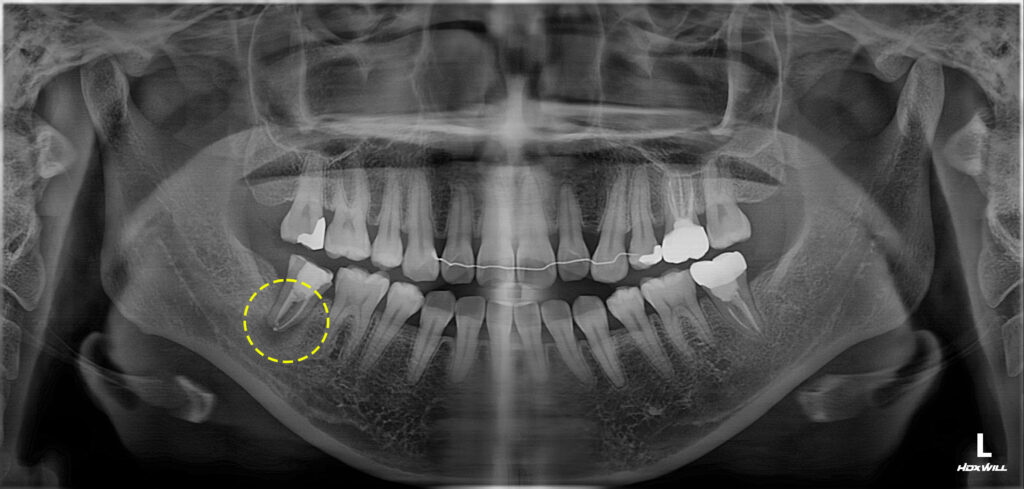

환자분께서는 오른쪽 아래 어금니 부위

신경치료를 받은지 2년 정도 지났는데

염증이 생겨 치료가 가능한지 체크를

원하신다며 저희 광화문치과에

내원해 주셨습니다.

작년 1월에 신경치료를 받으셨으며

3주 전부터 염증이 생겨 타 치과에서

약 처방을 받아 복용했다고 하셨는데요.

볼쪽으로 잇몸이 많이 부어 올라 있었고

치아의 흔들림도 있어 우선 재근관치료를

시도해본 뒤 필요 시 치아 재식술을 추가해서

진행하기로 하였습니다.